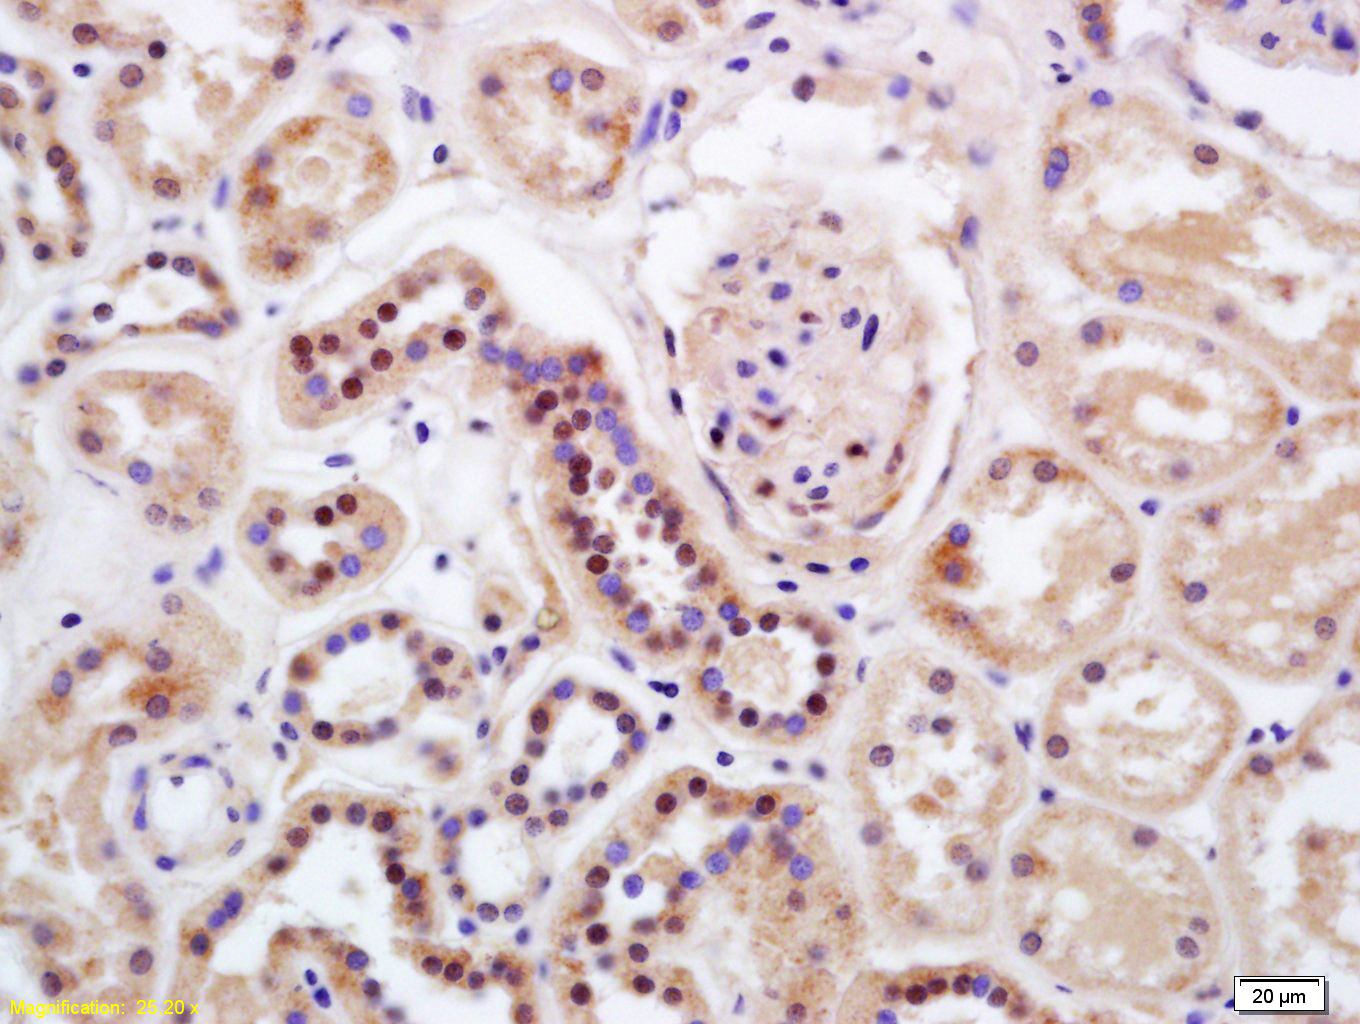

Tissue/cell: human kidney tissue; 4% Paraformaldehyde-fixed and paraffin-embedded; Antigen retrieval: citrate buffer ( 0.01M, pH 6.0 ), Boiling bathing for 15min; Block endogenous peroxidase by 3% Hydrogen peroxide for 30min; Blocking buffer (normal goat serum,C-0005) at 37℃ for 20 min; Incubation: Anti-HIPK2 Polyclonal Antibody, Unconjugated(bs-6353R) 1:200, overnight at 4°C, followed by conjugation to the secondary antibody(SP-0023) and DAB(C-0010) staining